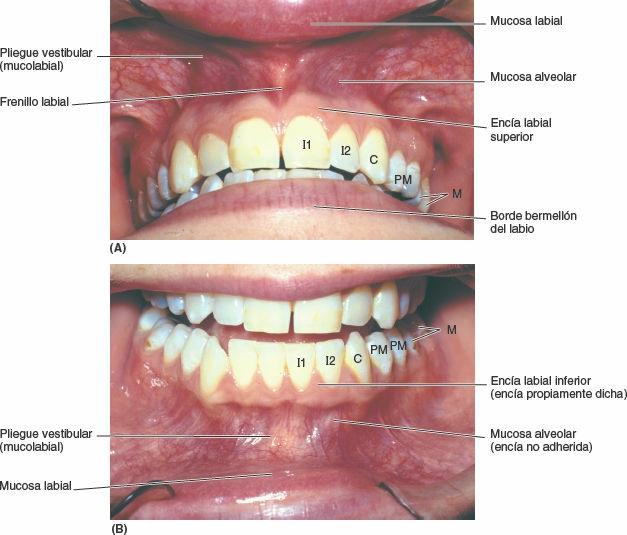

La zona de transición de los labios (considerada habitualmente como el labio propiamente dicho), de color que varía de pardo a rojo, continúa hasta la membrana mucosa bucal (mucosa labial) para transformarse en la mucosa que cubre la porción vestibular intrabucal de los labios (fig. 8-78). Los frenillos labiales son pliegues de la mucosa, de bordes libres, situados en la línea media; se extienden desde la encía vestibular hasta la mucosa de los labios superior e inferior, y el del labio superior es de mayor tamaño. A veces existen otros frenillos más pequeños lateralmente en las regiones vestibulares premolares.

Las encías se componen de tejido fibroso tapizado por una mucosa. La encía propiamente dicha (encía adherida) está firmemente unida a la parte alveolar de la mandíbula y a los procesos alveolares del maxilar, y a los cuellos de los dientes (figs. 8-76 y 8-78). La encía propiamente dicha adyacente a la lengua es la encía lingual superior e inferior; la encía adyacente a los labios y las mejillas es la encía labial o bucal (de la mejilla), respectivamente, maxilar y mandibular. La encía propiamente dicha suele ser rosada, punteada y queratinizada. La mucosa alveolar (encía no adherida) suele ser brillante, roja y no queratinizada. Los nervios y vasos que llegan a las encías, al hueso alveolar subyacente y al periodonto (que rodea las raíces del diente y lo fija en el alvéolo dentario) se presentan en la figura 8-79 A y C.